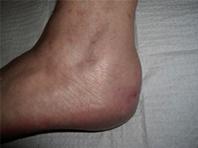

• נפיחות וכאב באזור חיבור גיד אכילס אל העצם מאחורי העקב